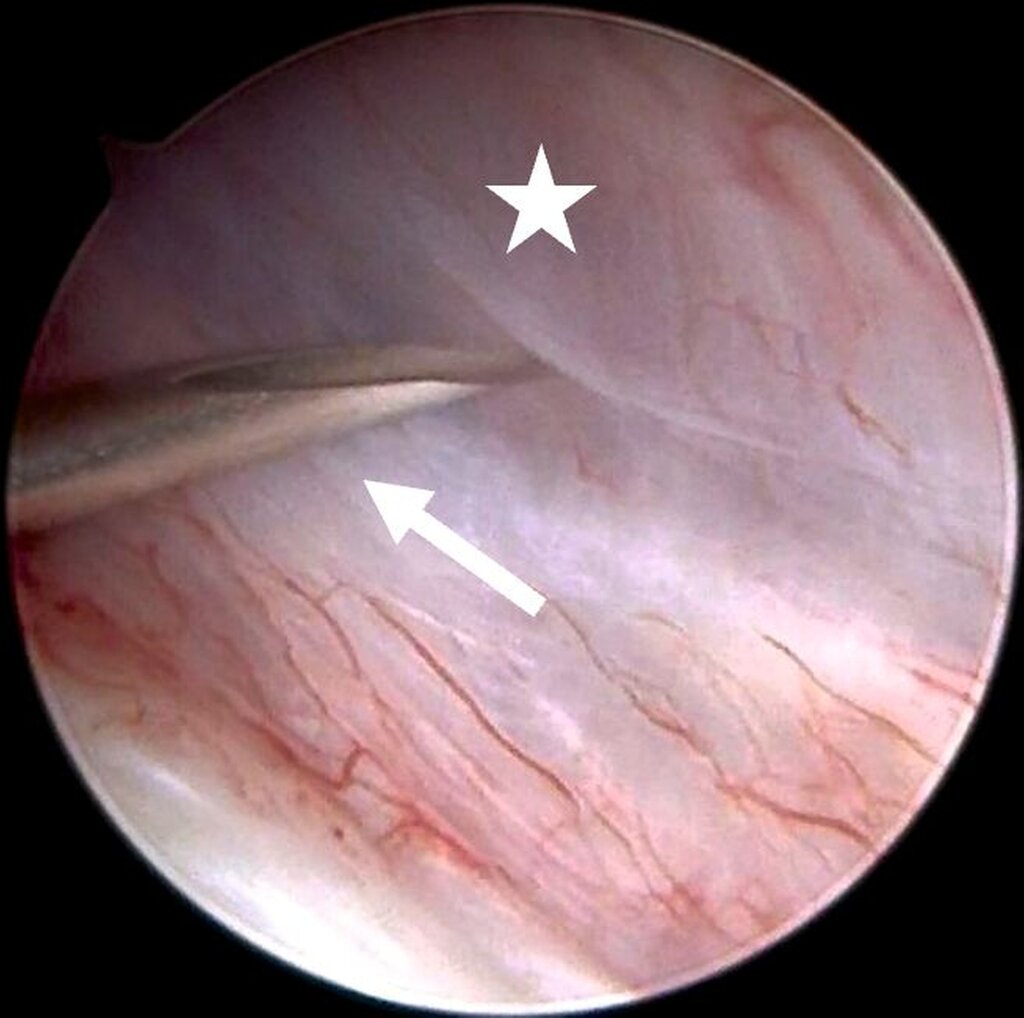

Eine Entzündung im Bereich der Gelenkkapsel (Synovitis) stellt eine häufige Ursache für arthrogen bedingte Beschwerden dar [Mercuri et al., 2025]. Neben der Darstellung des Gelenks und der Behandlung von Pathologien beruht ein positiver Effekt der Arthroskopie auf der Lavage des Gelenks. Dadurch können zum Beispiel proinflammatorische Mediatoren entfernt und intraartikuläre Adhäsionen gelöst werden [Soni, 2019]. Abbildung 2 zeigt die intraoperativen Befunde von zwei Patienten. Es wird jeweils der Übergang zwischen dem hinteren Aufhängungsband und der pars posterior des Discus articularis dargestellt.

Für die Kiefergelenksarthroskopie ist eine strukturierte Orientierung innerhalb des oberen Gelenkkompartiments essenziell. Hierfür haben sich die sogenannten „seven points of interest“ nach McCain etabliert (Abbildung 3) [Srouji et al., 2018]. Diese sieben anatomischen Referenzpunkte dienen der systematischen Beurteilung des Gelenks während des arthroskopischen Eingriffs. Zunächst werden das mediale synoviale Band und der Pterygoid-Schatten („pterygoid-shadow“) als Orientierungspunkte identifiziert. Es folgen die bilaminäre Zone – eine häufige Schmerzquelle – sowie die hintere Schräge der Gelenkeminenz. Die Beurteilung des Discus articularis gibt Auskunft über Verlagerungen und degenerative Prozesse. Es folgt die Beurteilung der intermediären Zone, die besonders anfällig für eine Perforation ist. Abschließend erfolgt die Begutachtung des vorderen Recessus. Dieser stellt den Eintritt der Punktionsstelle des Level-II-Zugangs dar [Srouji et al., 2018].